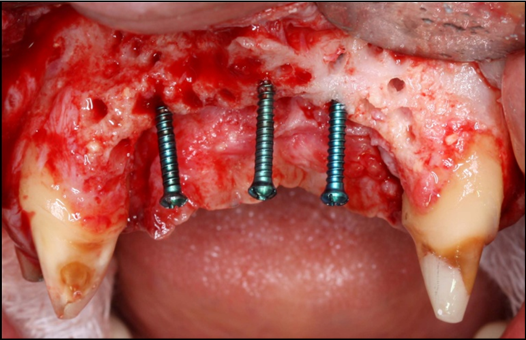

The surgical procedure was done under intravenous sedation using Fentanyl and Versed. Local anesthetic was used and a supra-crestal horizontal incision made on the palatal aspect of the anterior maxilla. A mucoperiosteal flaps were elevated, exposing a severely resorbed ridge of the pre-maxilla (Figure 2). Decortication was conducted with a round carbide bur in order to perforated the cortical aspect of the bone and expose the cancellous bone, to increase vascularity to the recipient site. Three screws were fixed parallel to the adjacent teeth, serving as “tent pole”. The screws had 14 mm length and approximately 6-8 mm of the tenting screws were exposed to the oral cavity (Figure 3). An absorbable collagen sponge (ACS) carrier/matrix was embedded with 12 mg of rhBMP-2 at 1.5 mg/mL (Infuse® Medtronic Sofamor Danek, Memphis, TN, USA) and allowed to absorb for approximately 20 min. The rhBMP-2/ACS was cut into strips, half of the strips were added to the natural bone mineral component derived from bovine bone (Geistlich Bio-Oss® granules small - 0.25 to 1 mm, Geistlich Pharma, Germany). Initially, some strips of rhBMP-2/ACS were placed over the buccal aspect of the residual alveolar ridge of the pre-maxilla, followed by strips mixed with bovine bone (Figure 4). The three screws were fully covered by rhBMP-2/ACS strips. Finally, a titanium mesh was adapted over the entire rhBMP-2/ACS graft and fixed with 2 monocortical screws, one on the buccal aspect and one on the palatal aspect of the ridge, respecting a 2 mm distance from the mesh to the adjacent teeth (Figure 5). Extensive undermining incision was conducted on the apical aspect of the buccal flap in order to achieve primary closure.

Figure 3.Frontal view of the pre-maxilla after elevation of amucoperiosteal flap. Note 6-8 mm of the tenting screws length are exposed.